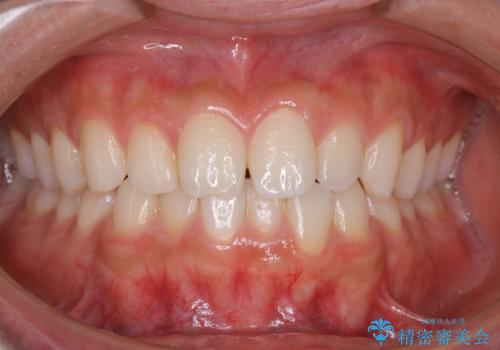

ぱっと見しっかり磨けているように見えますが、染だしをしてみると歯ぐきの境目などに磨き残しがあることがわかります。定期的に染め出しを行い、日々のブラッシングの癖や磨き残しを把握することで、改善するべきポイントが明確に発見されます。